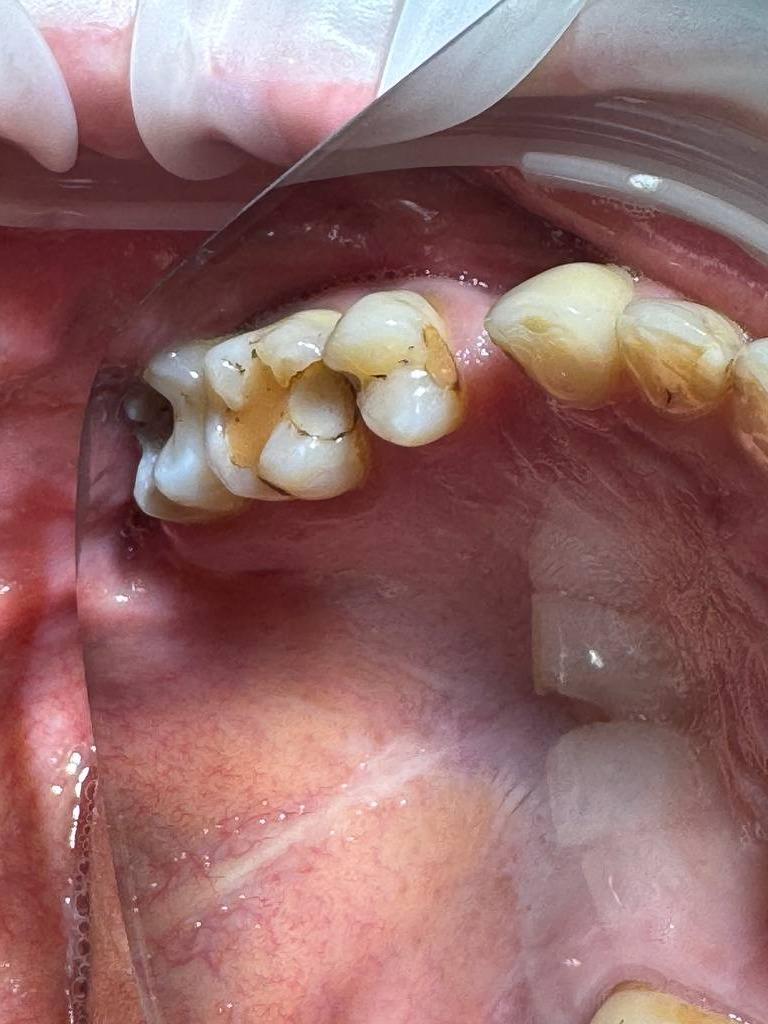

Пациент40 лет, жалобы на боль от термических и химических раздражителелй. Произведено лечение кариеса 14,15 зубов под микроскопом в условиях седации.